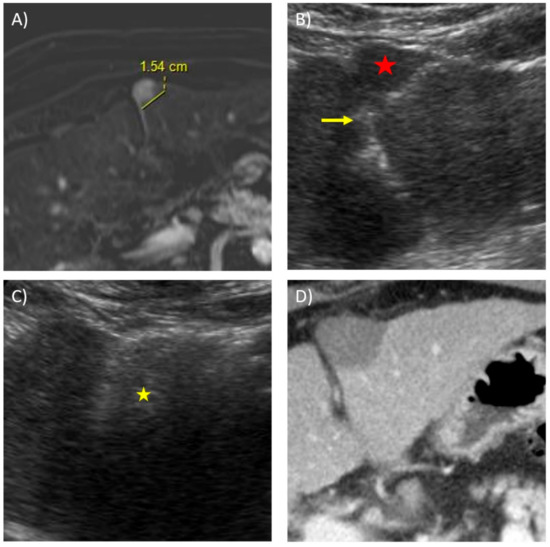

- Rhim, H.; Lee, M.H.; Kim, Y.-S.; Choi, D.; Lee, W.J.; Lim, H.K. Planning Sonography to Assess the Feasibility of Percutaneous Radiofrequency Ablation of Hepatocellular Carcinomas. Am. J. Roentgenol. 2008, 190, 1324–1330. [Google Scholar] [CrossRef]

- Lee, M.W.; Kim, Y.J.; Park, H.S.; Yu, N.C.; Jung, S.I.; Ko, S.Y.; Jeon, H.J. Targeted Sonography for Small Hepatocellular Carcinoma Discovered by CT or MRI: Factors Affecting Sonographic Detection. Am. J. Roentgenol. 2010, 194, W396–W400. [Google Scholar] [CrossRef]

- Hui, T.; Huang, I.; Lau, W.; Pua, U. Does intra-tumoural fat on MRI predict visibility of small (≤3 cm) hepatocellular carcinomas during ultrasound-guided tumour ablation? Clin. Radiol. 2018, 73, 254–258. [Google Scholar] [CrossRef]

- Kim, P.N.; Choi, N.; Rhim, H.; Rha, S.E.; Hong, H.P.; Lee, J.; Choi, J.-I.; Kim, J.W.; Seo, J.W.; Lee, E.J.; et al. Planning Ultrasound for Percutaneous Radiofrequency Ablation to Treat Small (≤3 cm) Hepatocellular Carcinomas Detected on Computed Tomography or Magnetic Resonance Imaging: A Multicenter Prospective Study to Assess Factors Affecting Ultrasound Visibility. J. Vasc. Interv. Radiol. 2012, 23, 627–634. [Google Scholar] [CrossRef]